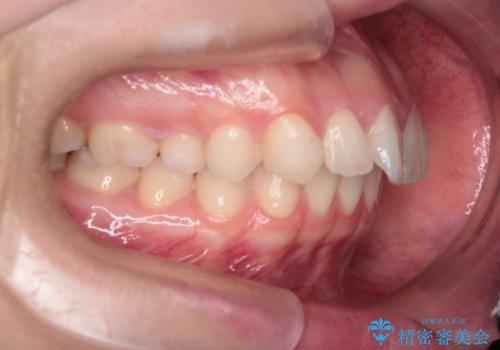

- 患者様は、上下顎の歯列不正と前歯部の突出感を主訴としてご来院されました。診断の結果、上顎左右第一小臼歯を抜歯することでスペースを確保し、歯列全体を整える方針としました。本来はワイヤー矯正が推奨されるケースですが、患者様のご希望により、透明なマウスピース型矯正装置「インビザライン」を使用した治療計画を立案しました。治療期間は約3年で、奥歯の噛み合わせを維持しながら、徐々に前歯の位置を整えました。